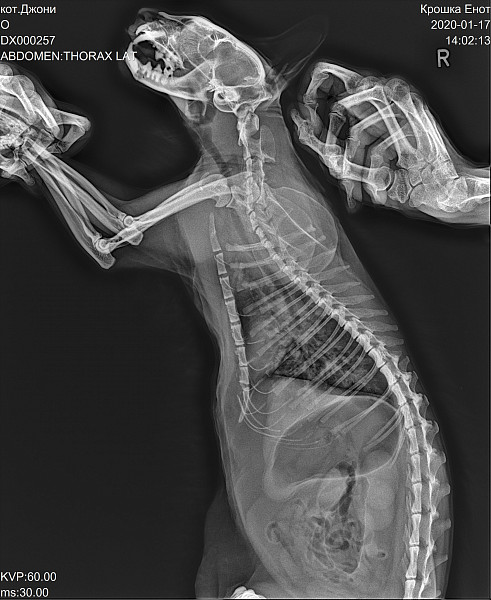

Общий анализ крови делали 7 декабря (по нему поставлен диагноз аллергия). Позже при лечении отита быд сделан рентген для поиска причин затрудненного дыхания(посторонних предметов и опухолей не выявлено) Результаты:.

По рентгену выраженные изменения в легких. Я бы задумалась об антибиотикотерапии (например, синулокс или юнидокс).